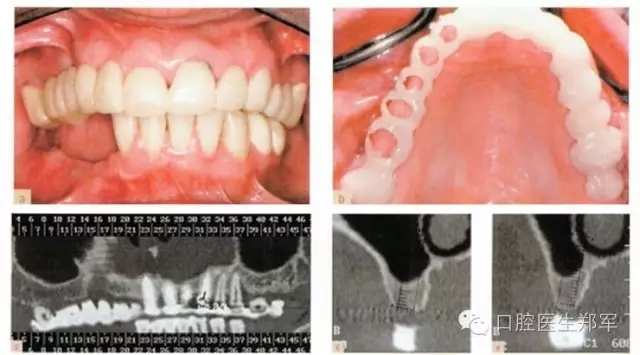

•最終評估暫時修復體的美學和功能,將暫時修復體轉移到最終修復體上(圖11);

•通過交叉上牙合架技術復制暫時修復體到最終修復體上(圖12)。

圖11 a和b 種植體基臺和基牙的預備。c 再次評估暫時修復體并確認其功能、美學和穩(wěn)定性。d 根據(jù)回切硅膠導板和暫時修復體交叉上牙合架技術修整最終修復體蠟型。 |

圖12 a和b最終修復體(圖由修復學專家Dr 0 Gelfan, Professor Z Artzi , and Mr B lndig.提供) |